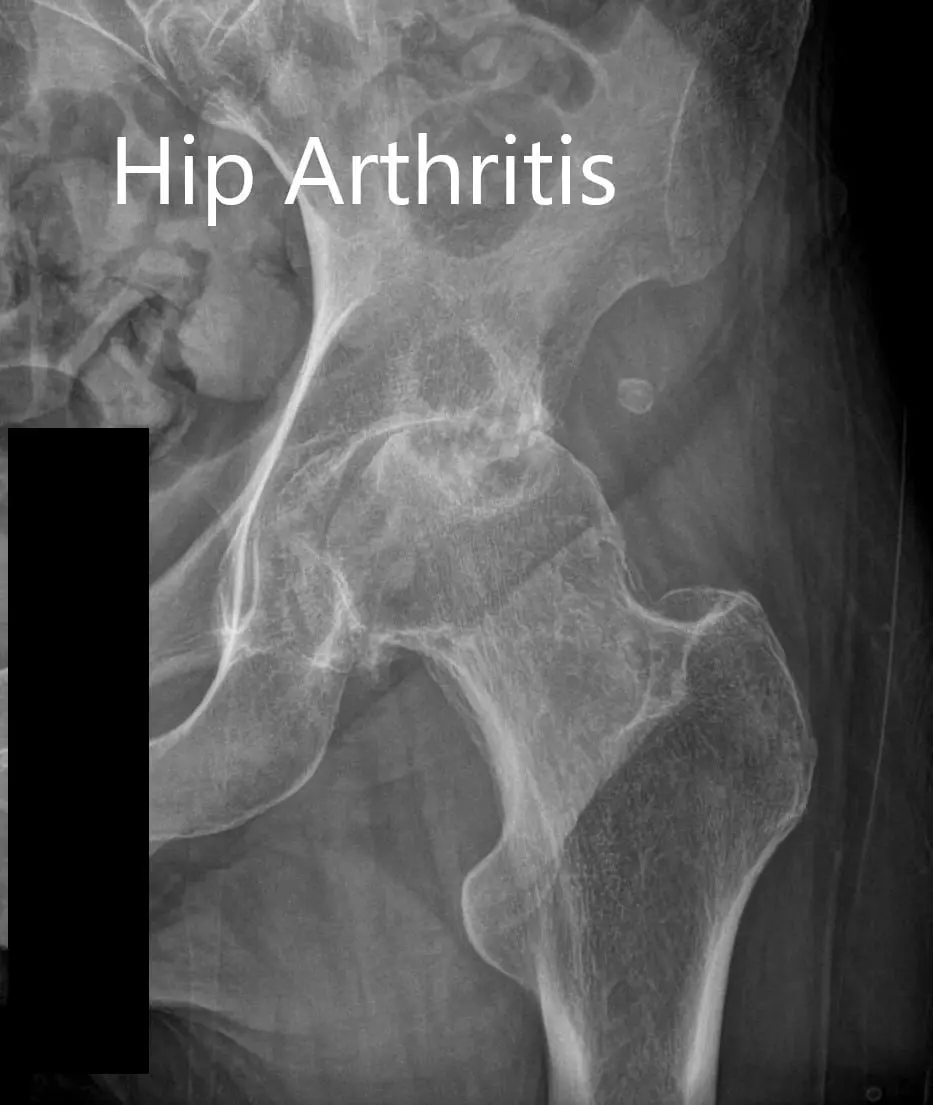

Imaging revealed osteoarthritic changes in bilateral hips (right greater than left). Considering the patient’s comorbidities and lifestyle limiting hip arthritis, he was advised bilateral total hip replacement. Risks, benefits, and alternatives were discussed with the patient at length. He decided to go for right hip replacement first.

Preoperative AP and lateral views of the right hip joint.

Preoperative X-ray of the left hip showing AP and lateral views.